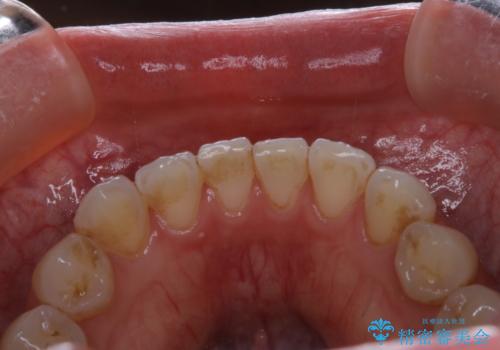

- 専門的な機械ででしっかりとキレイにクリーニングしてほしいとのことでしたPMTC60分コースを行いました。

PMTCは、歯に付着した汚れを除去していくため、着色が気になる場合にも行うことができます。ご自身でのセルフケアだけで着色を落とそうとすると、逆に歯を傷つけてしまったり、精密に汚れを除去できないこともあります。また、日常生活で着色しやすい飲食物を避けたりすることはストレスに感じてしまったり、あまり現実的ではありません。

毎日丁寧に歯磨きをしていても、日常生活での飲食物などにより着色してしまうことはあります。PMTCでは、歯の表面の凸凹にミネラルを補給して、ツルツルの表面に仕上げます